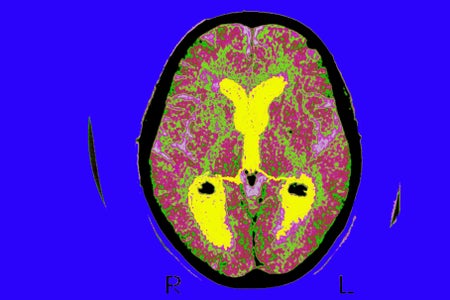

Treating Alzheimer’s Before It Takes Hold

Researchers are giving drugs to healthy people in hope of clearing away toxic proteins in the brain and preventing neurodegeneration.